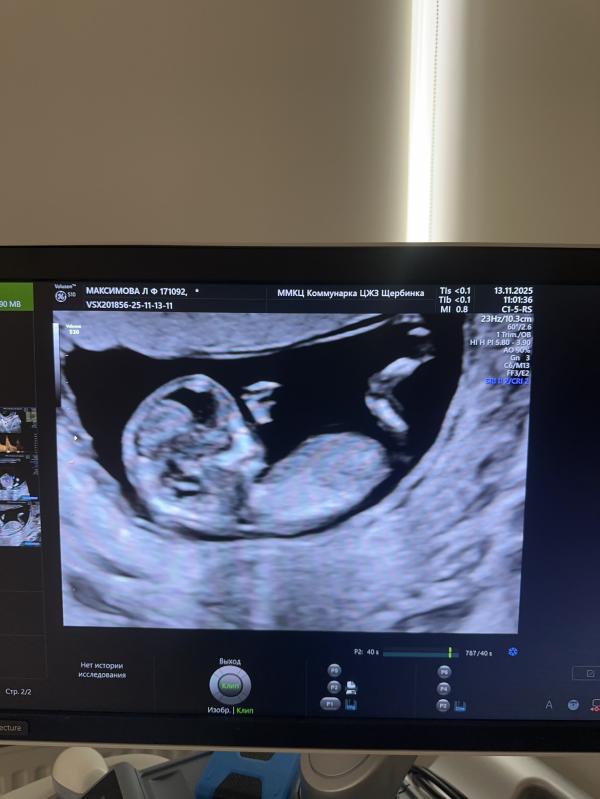

Прошла скрининг, все хорошо. 🙏

Предположительно сказали - девочка , так вот , теперь вопрос, кому так говорили , совпало?